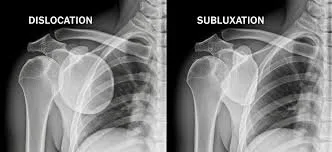

Subluxation vs. Dislocation: What’s the Difference?

• A subluxation is a partial loss of joint alignment. The joint surfaces shift out of their ideal position but still maintain some contact.

• A dislocation is a complete loss of joint contact, where the joint surfaces are no longer touching.